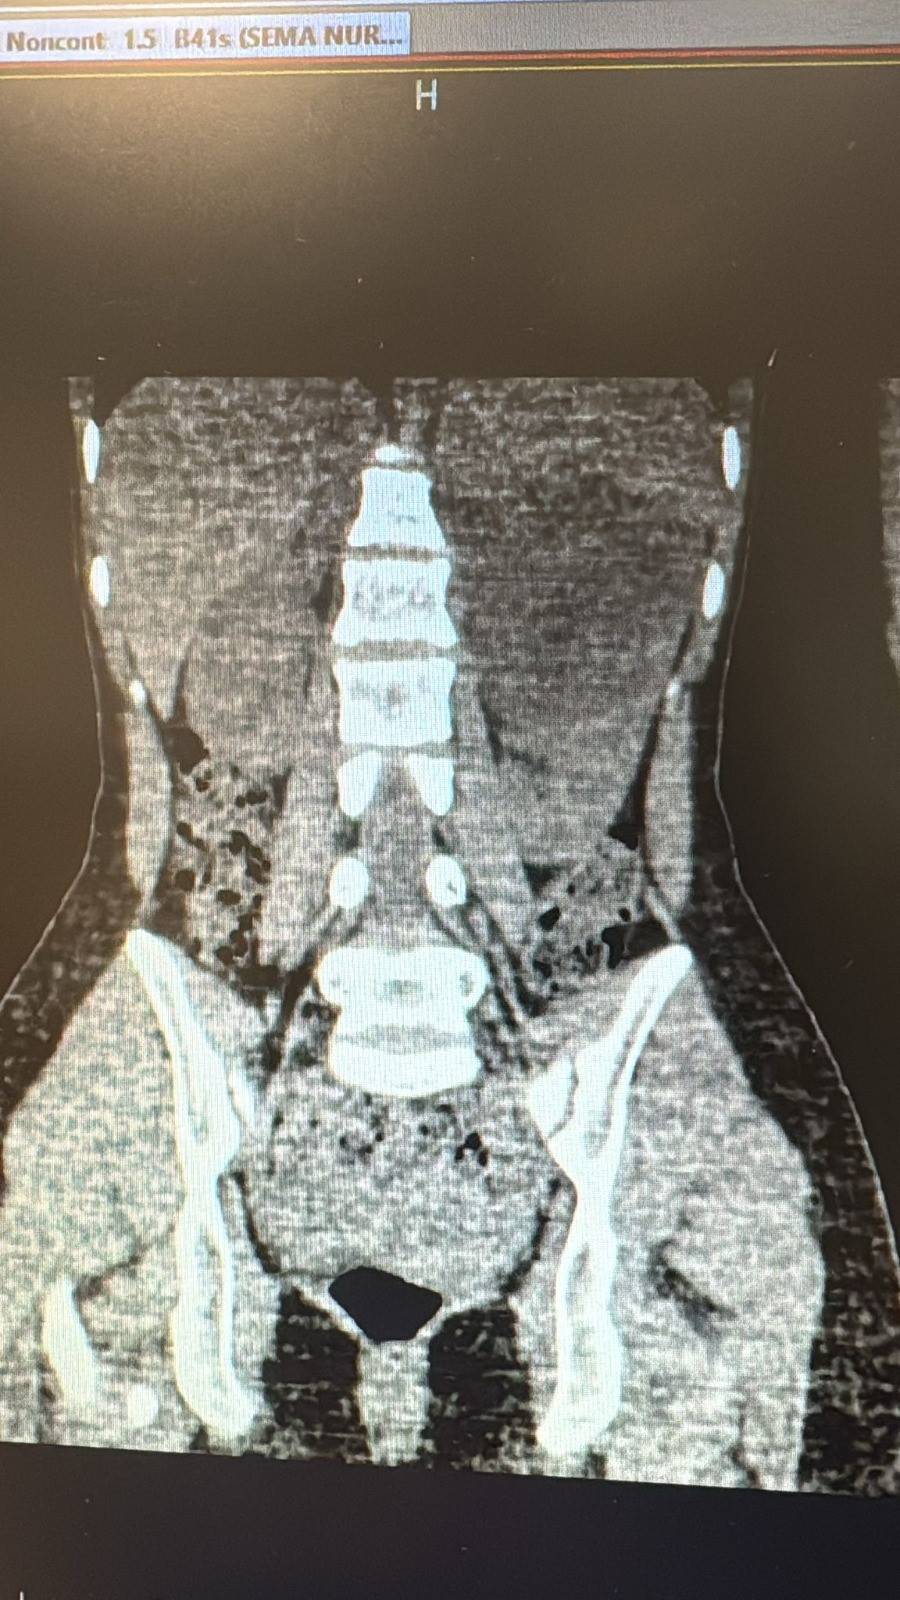

Şanlıurfa Viranşehir Devlet Hastanesi’nde, 18 yaşındaki bir hastanın sol böbreğinde tespit edilen yaklaşık 10 santimetre çapındaki kist, laparoskopik (kapalı) yöntemle başarıyla çıkarıldı.

Uzun süredir sol yan ağrısı şikâyeti bulunan kadın hasta, dış merkezde yapılan tetkiklerde sol böbrekten kaynaklanan, böbrek ve dalağı iterek komşu organlara yapışıklık gösteren büyük bir kist tespit edilmesi üzerine Viranşehir Devlet Hastanesi’ne sevk edildi.

Hastanede yapılan değerlendirmelerin ardından kistin cerrahi yöntemle alınmasına karar verildi. Üroloji kliniğinde gerçekleştirilen operasyonda, 10 santimetre boyutundaki böbrek kisti laparoskopik yöntemle, 2 adet 5 milimetre ve 1 adet 10 milimetrelik kesi kullanılarak çıkarıldı. Böylece hasta, açık cerrahiye gerek kalmadan tedavi edildi. Ameliyat sonrası takiplerinde herhangi bir komplikasyon gelişmeyen hasta, sağlığına kavuşarak taburcu edildi.